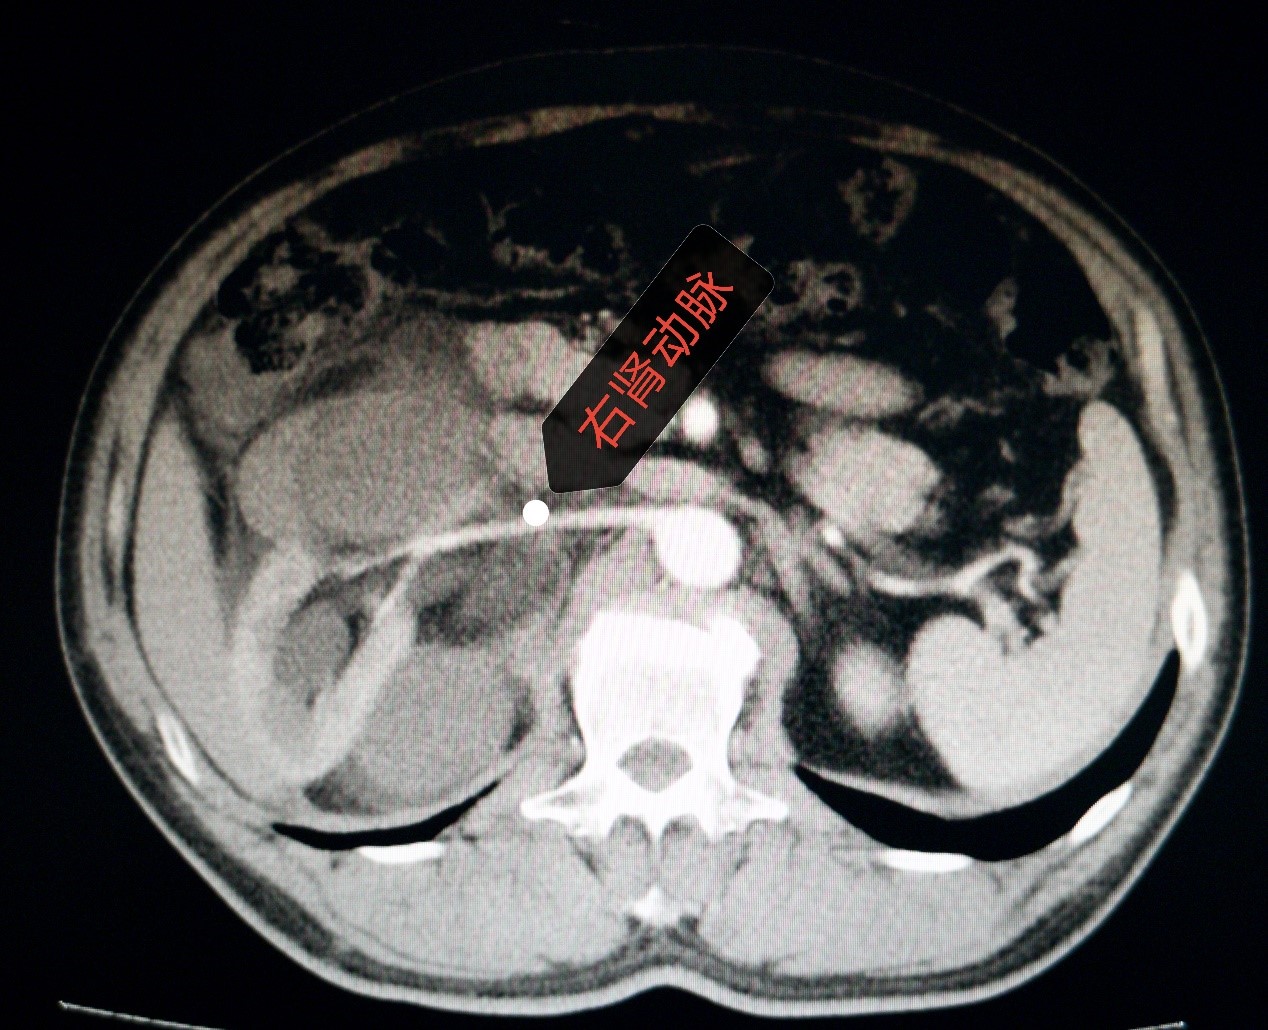

近日,西院肿瘤外科成功为一腹膜后脂肪肉瘤复发患者开展手术。患者于1年半前在外地某三甲医院被诊断为“腹膜后肿物”,行腹膜后肿物切除术,术后病理诊断为“腹膜后脂肪肉瘤”。此后定期复查,1月前,患者自觉左侧腹部可触及包块,伴疼痛,腹胀,食欲下降,消瘦明显。在外院查腹部彩超提示:腹膜后肿物。患者为进一步治疗,来我院。入院后完善检查,进一步明确诊断。全腹增强CT提示:右中腹见团块状混杂密度影,形态不整,右肾变形,内部密度不均,与下腔静脉、胰头、十二指肠,右侧腰大肌关系密切,增强扫描呈混杂密度影。肿瘤外科全体医生对患者病情进行了细致详尽的术前讨论。患者1年半前行腹膜后脂肪肉瘤切除术,此次考虑为腹膜后脂肪肉瘤复发,肿瘤较大,与周围器官关系密切,尤其紧邻下腔静脉,二次手术风险极大,一旦发生下腔静脉意外撕裂,可能造成空气栓塞等致命性危险。全科医生一起反复仔细查阅增强CT,制定详尽的手术计划。并对可能出现的风险及意外进行预判,提出解决方案。与患者家属沟通,详细交待病情,说明治疗方案及手术风险。

在进行了充分的围手术期准备后,手术如期进行,手术由张凤祥院长、刘德智主任、郭云峰医生、包巴特尔医生共同完成。术中探查所见:肿瘤位于右侧腹腹膜后,上方达肝下缘并伸向后纵膈,下方达右侧髂窝水平,内侧包绕下腔静脉前后方,外侧达升结肠侧腹壁,前方侵犯右半结肠系膜,后方与右侧腹膜后广泛粘连,右肾及肾血管、右输尿管包裹于肿瘤中。术中考虑为腹膜后脂肪肉瘤复发,决定行腹膜后脂肪肉瘤联合右半结肠、右肾、右肾上腺切除。肿物与周围组织器官粘连致密,活动度差,切除极其困难。手术历时四个半小时,顺利将腹膜后肿瘤与右半结肠、右肾上腺、右肾一并完整切除。未出现副损伤,患者术后恢复良好。